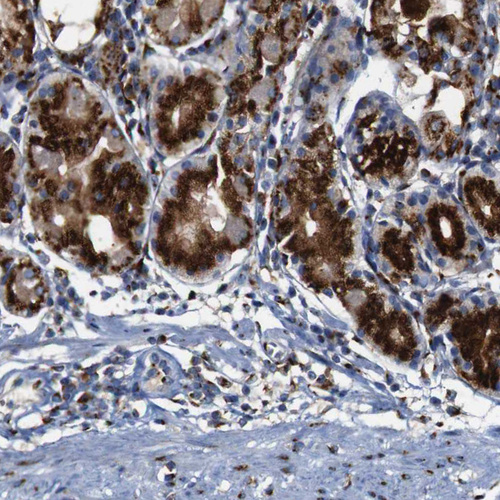

Immunohistochemical staining of human cerebral cortex, colon, kidney and testis using Anti-TGOLN2 antibody HPA012609 (A) shows similar protein distribution across tissues to independent antibody HPA012723 (B).